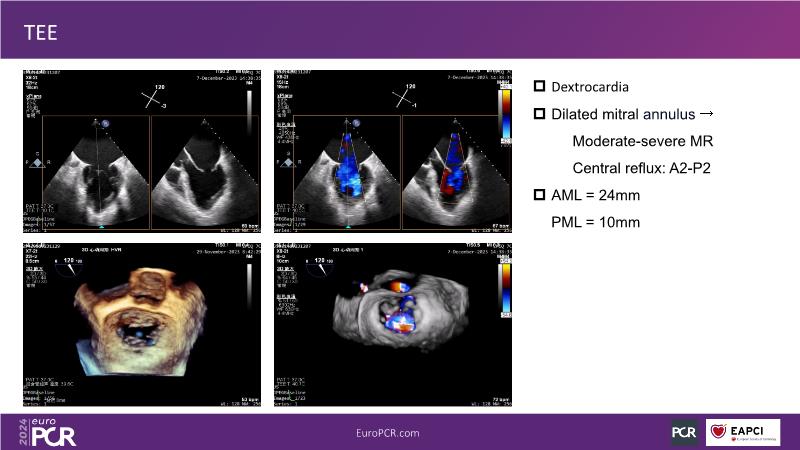

Watch this session to gain insights into the clinical evidence of mitral TEER therapy for the Asian population, learn techniques for implanting a MitraClip in patients with challenging anatomy, and understand how to use the four clip sizes for optimal outcomes. The session also covers educational aspects of clipping in dextrocardia, the benefits of reserve bending of the transseptal needle for tenting and puncture, new steering maneuvers for dextrocardia patients, and the importance of understanding anatomy and collaborating closely with the echo team for success.